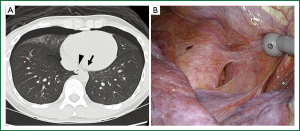

A previously healthy 35-year-old man without a history of smoking presented with left chest pain. Chest X-ray showed simultaneous bilateral pneumothorax. The pneumothorax was large on the right side (≥3 cm apex-to-cupola distance) and small on the left (<3 cm). He was clinically stable. Chest computed tomography (CT) scans revealed small bullae on both lungs. A small air space between the esophagus and aorta was also observed, suggesting pleuro-pleural communication, as confirmed later (Figure 1A). The patient consented to bilateral bullectomy.

Video-assisted thoracoscopic surgery was planned first on the right side which had the large pneumothorax, and a chest tube was inserted into the left side in the operating room and showed no evidence of air leaks. During the right thoracoscopy, water that was poured to test for air leaks was observed escaping from the right pleural cavity to the left-side chest tube. Pleuro-pleural communication was suspected but not detected. Staple bullectomy and coverage with a polyglycolic acid sheet and fibrin glue were performed for the bulla on the right middle lobe and then for the bullae on the left upper lobe. Repeated inspection revealed a 2-cm-long pleural window posterior to the inferior pulmonary ligament, between the aorta and esophagus (Figure 1B). The window was packed with a polyglycolic acid sheet and fibrin glue and covered using a collagen patch coated with human fibrinogen and thrombin. The postoperative course was uneventful.